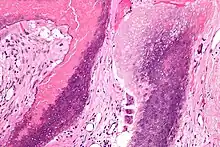

Microscopie: Pilomatrixome. HE, x24. Présence d'une tumeur calcifiée dans le derme profond.

Microscopie: Pilomatrixome. HE, X100. Présence de cellules "fantômes" partiellement calcifiées et de cellules géantes multinucléées à corps étrangers